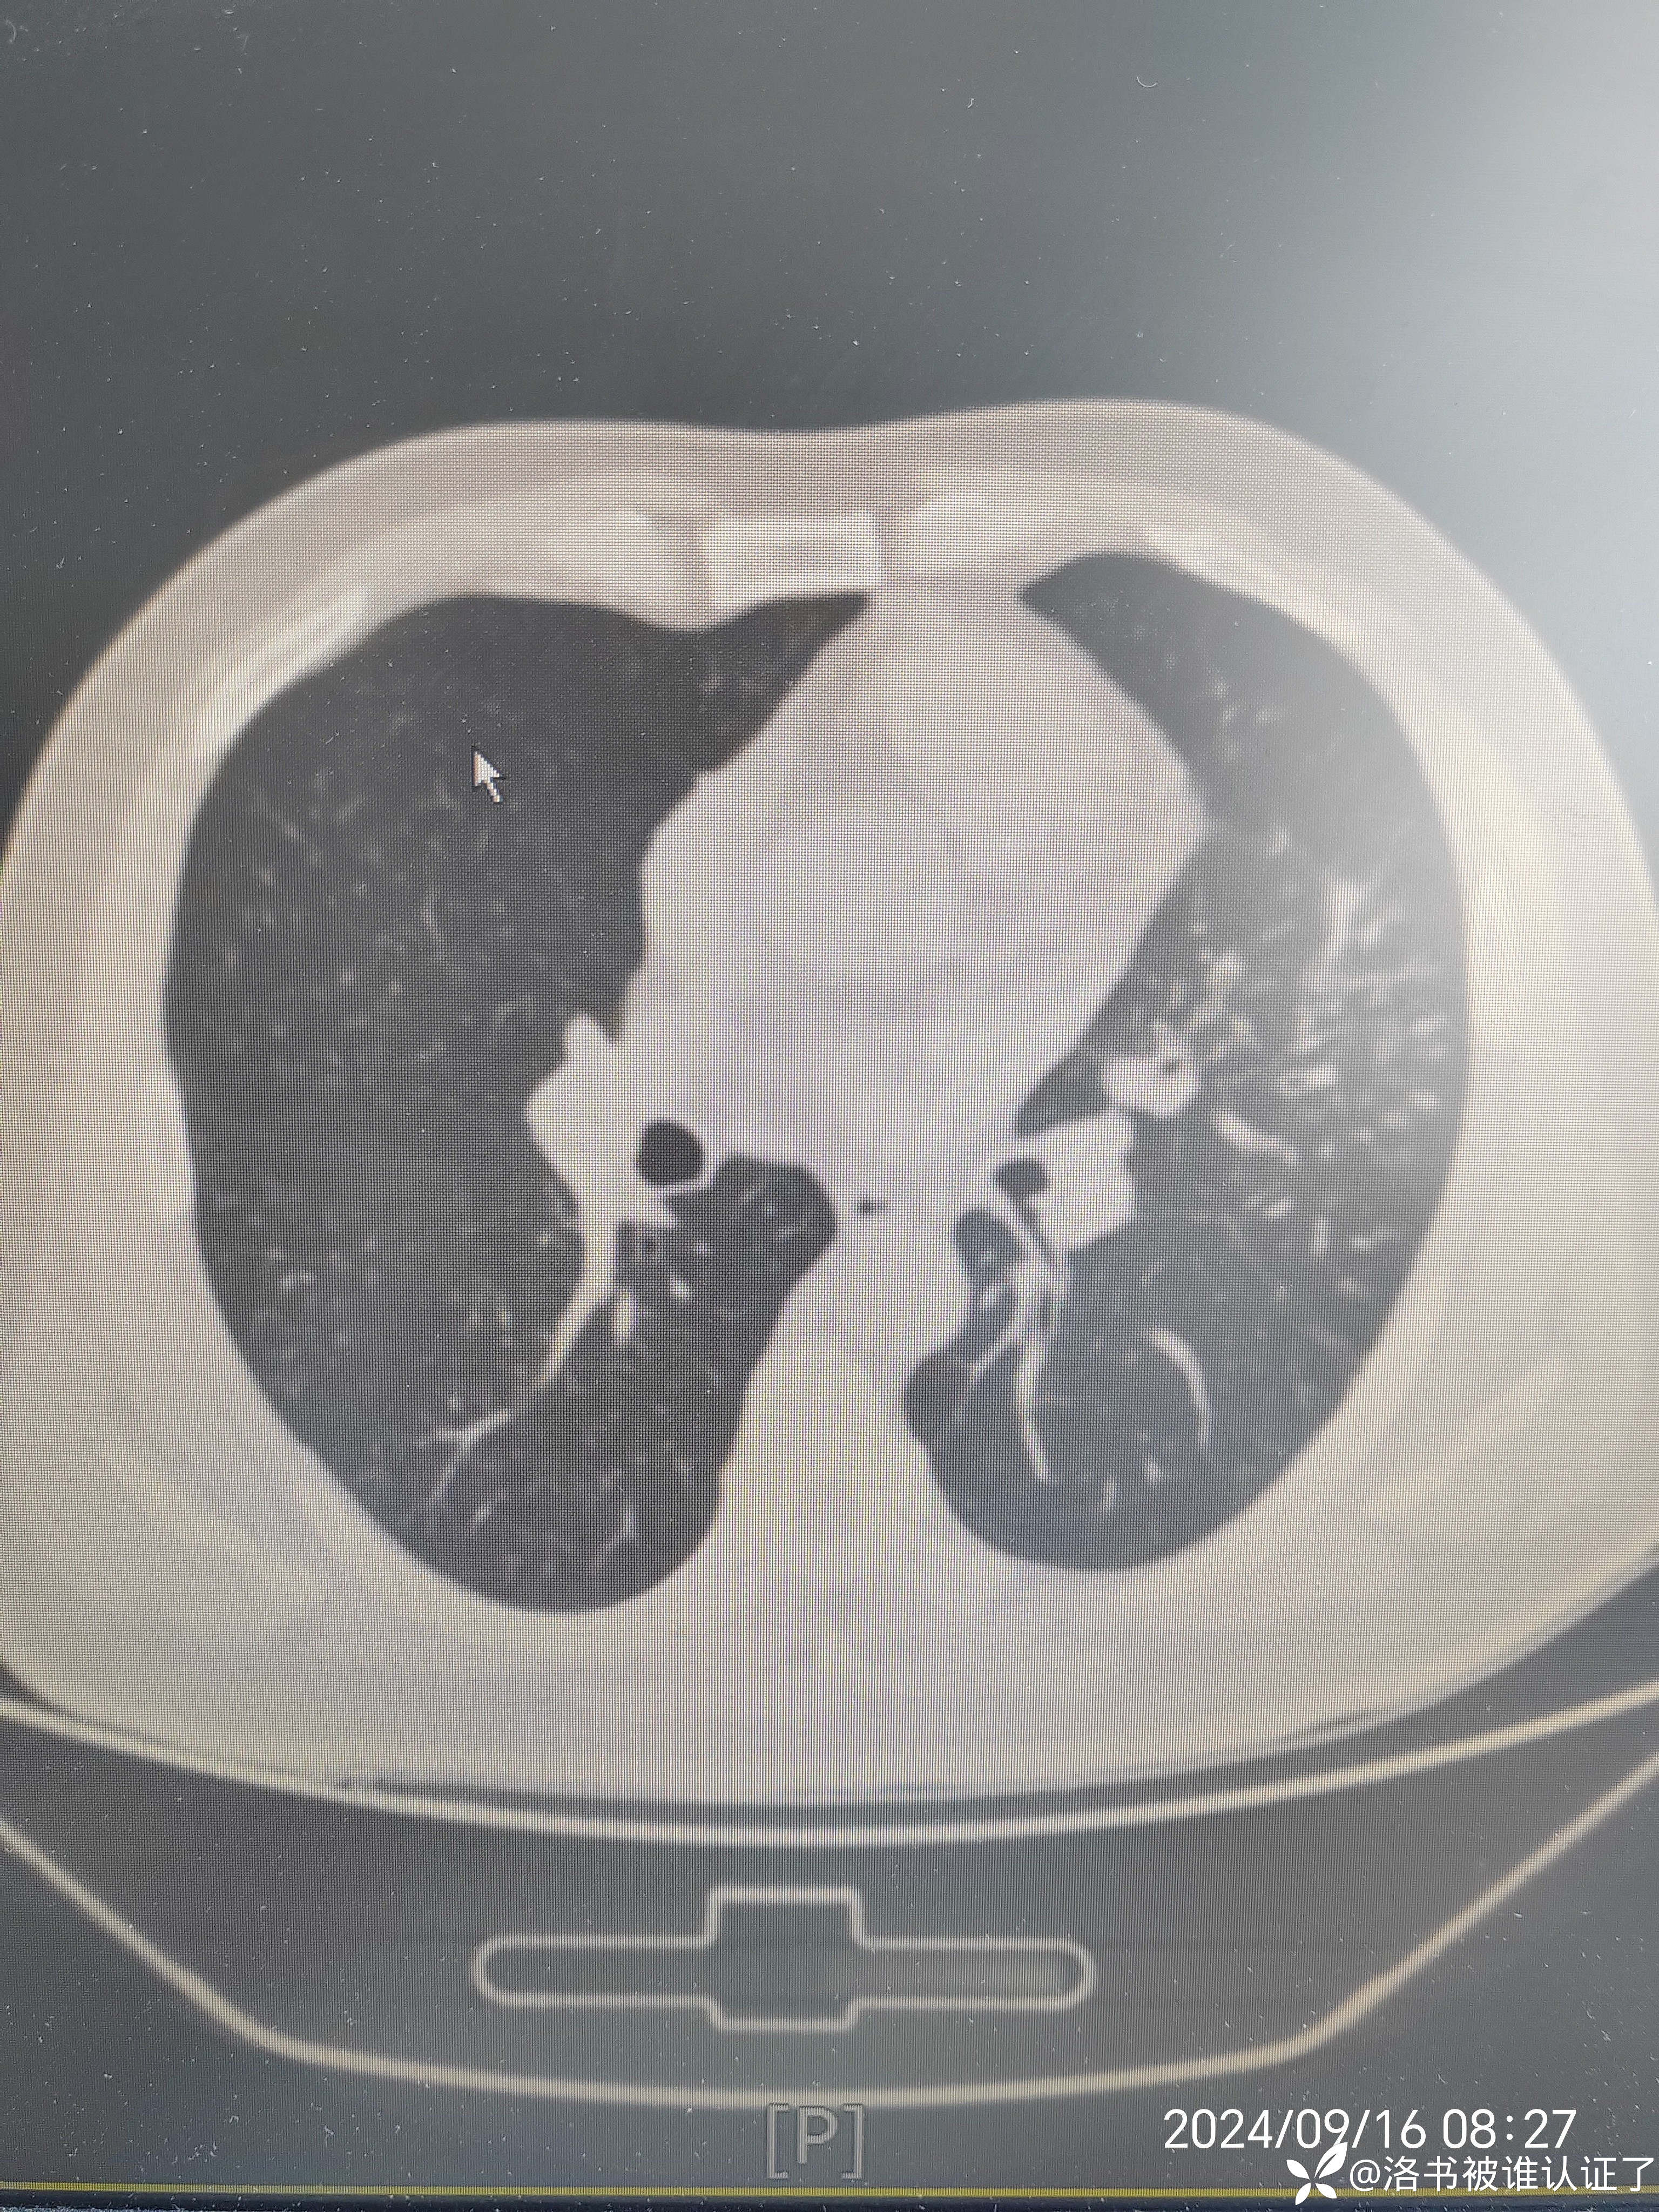

【检查】胸部CT示肺炎。

【临床诊断】:肺炎